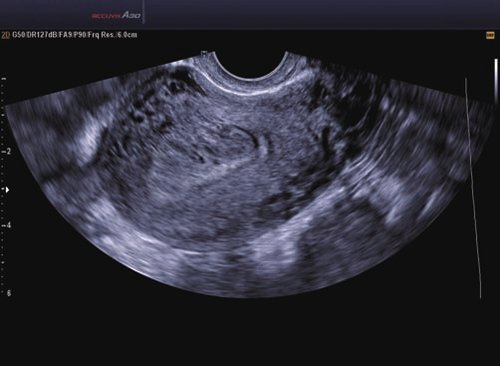

Das Samsung Accuvix A30 ist ein hochwertiges Ultraschallsystem, das mit seiner 3D-Technologie herausragende Ergebnisse ermöglicht. Das Sonographiegerät besitzt 5 Sondenanschlüsse und ist mit 20 unterschiedlichen Schallköpfen kompatibel. Mit dem A30 können Schallköpfe vom Typ Konvex, Mikrokonvex, 3D-Konvex, CW, Phased Array, Linear und Endokavitär verwendet werden. Bei zwei der Sonden handelt es sich um S-VUE Ultraschallsonden, die durch ihre höhere Bandbreite noch feinere Scans erzeugen.

12 V2-6 3D Konvex 2-6 Abdomen, Frauenheilkunde und Geburtshilfe

13 V4-8 3D Konvex 4-8 Abdomen, Frauenheilkunde und Geburtshilfe

15 EC4-9IS Endokavitär 4-9 Frauenheilkunde und Geburtshilfe, Endovaginal, Fetal, Urologie

16 VR5-9 Endokavitär 5-9 Frauenheilkunde und Geburtshilfe, Urologie